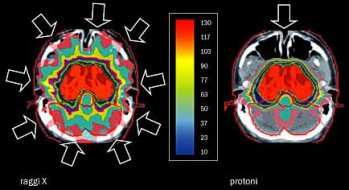

Nella figura b, a sinistra, è mostrata, in una opportuna scala di colori, la distribuzione della dose (energia per unità di massa) data a un tumore encefalico con nove fasci di raggi X incrociati. Il tasso di cura dei tumori irradiati crescerebbe ulteriormente se si potesse aumentare la dose al tumore senza aumentare quella data ai tessuti sani vicini. Qui interviene l’adroterapia.

b. Distribuzione della dose, cioè dell’energia data per unità di massa, in un trattamento di un tumore con nove fasci di raggi X incrociati (a sinistra) o con un fascio di protoni proveniente da una sola direzione (a destra).

Confrontando nella figura b l’immagine di sinistra con quella di destra, è evidente che – proprio per questa proprietà – i tessuti sani sono molto meno irradiati che non nel caso dei raggi X. L’efficacia clinica dei protoni è identica a quella dei raggi X ma risparmiano meglio i tessuti sani. Se si potessero costruire oggi acceleratori di protoni da 200 MeV piccoli e poco costosi quanto i linac per elettroni, potremmo utilizzare la protonterapia al posto della radioterapia con raggi X. Purtroppo però il più piccolo ciclotrone per protoni è superconduttore e ha un diametro di tre metri e pesa più di cinquanta tonnellate.